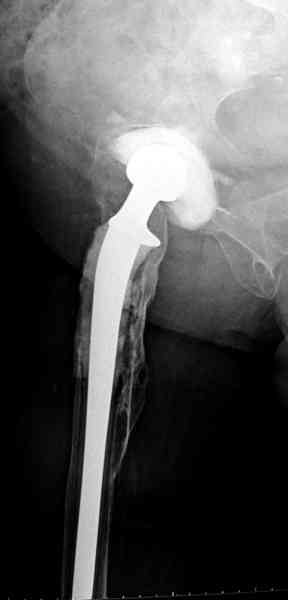

Представляю вашему вниманию снимки (прошу прошения за качество снимков) больной 48 лет с ревматоидным артритом, которой был сделан тотальный эндопротез справа,

контрольный снимок сделали только на 21день после операции (№1) и с интервалом 5 дней второй снимок (№2)

Судя по всему, произошел раскол наружной стенки бедра и ножка находится вне костного канала. В таком случае

решение одно - удаление ножки и установка новой в расчете на дистальную фиксацию. Конктреную модель подсказать тяжело из-за низкого качества Р-грамм.

Приглашенный хирург установил ревизионный вариант бедренного компонента без замены ацетабулярного компонента, что осложнилось нагноением и свищами на уровне сустава и средней трети бедра. После двухгодичного безуспешного лечения перевязками и антибиотиками больная обратилась к нам на консультацию.

Для спейсера в бедро использовал старый длинный бедренний компонент меньшего диаметра, облепленный со всех сторон цементом с антибиотиком.

Наглухо ушитая рана с дренажом зажила первично, после чего с больной потерял контакт, и только недавно, через 8 лет я осмотрел её. Она без проблем нагружает на конечность и передвигается с помощью трости. От окончательной операции по реконструкции отказывается, довольная результатом.

Имеются литературные данные, когда спейсер держали не более 6 месяцев, но этот случай бьет все рекорды, может быть для наших людей, обременных финансовыми трудностями, нужна другая шкала оценки сроков нахождения спейсеров.